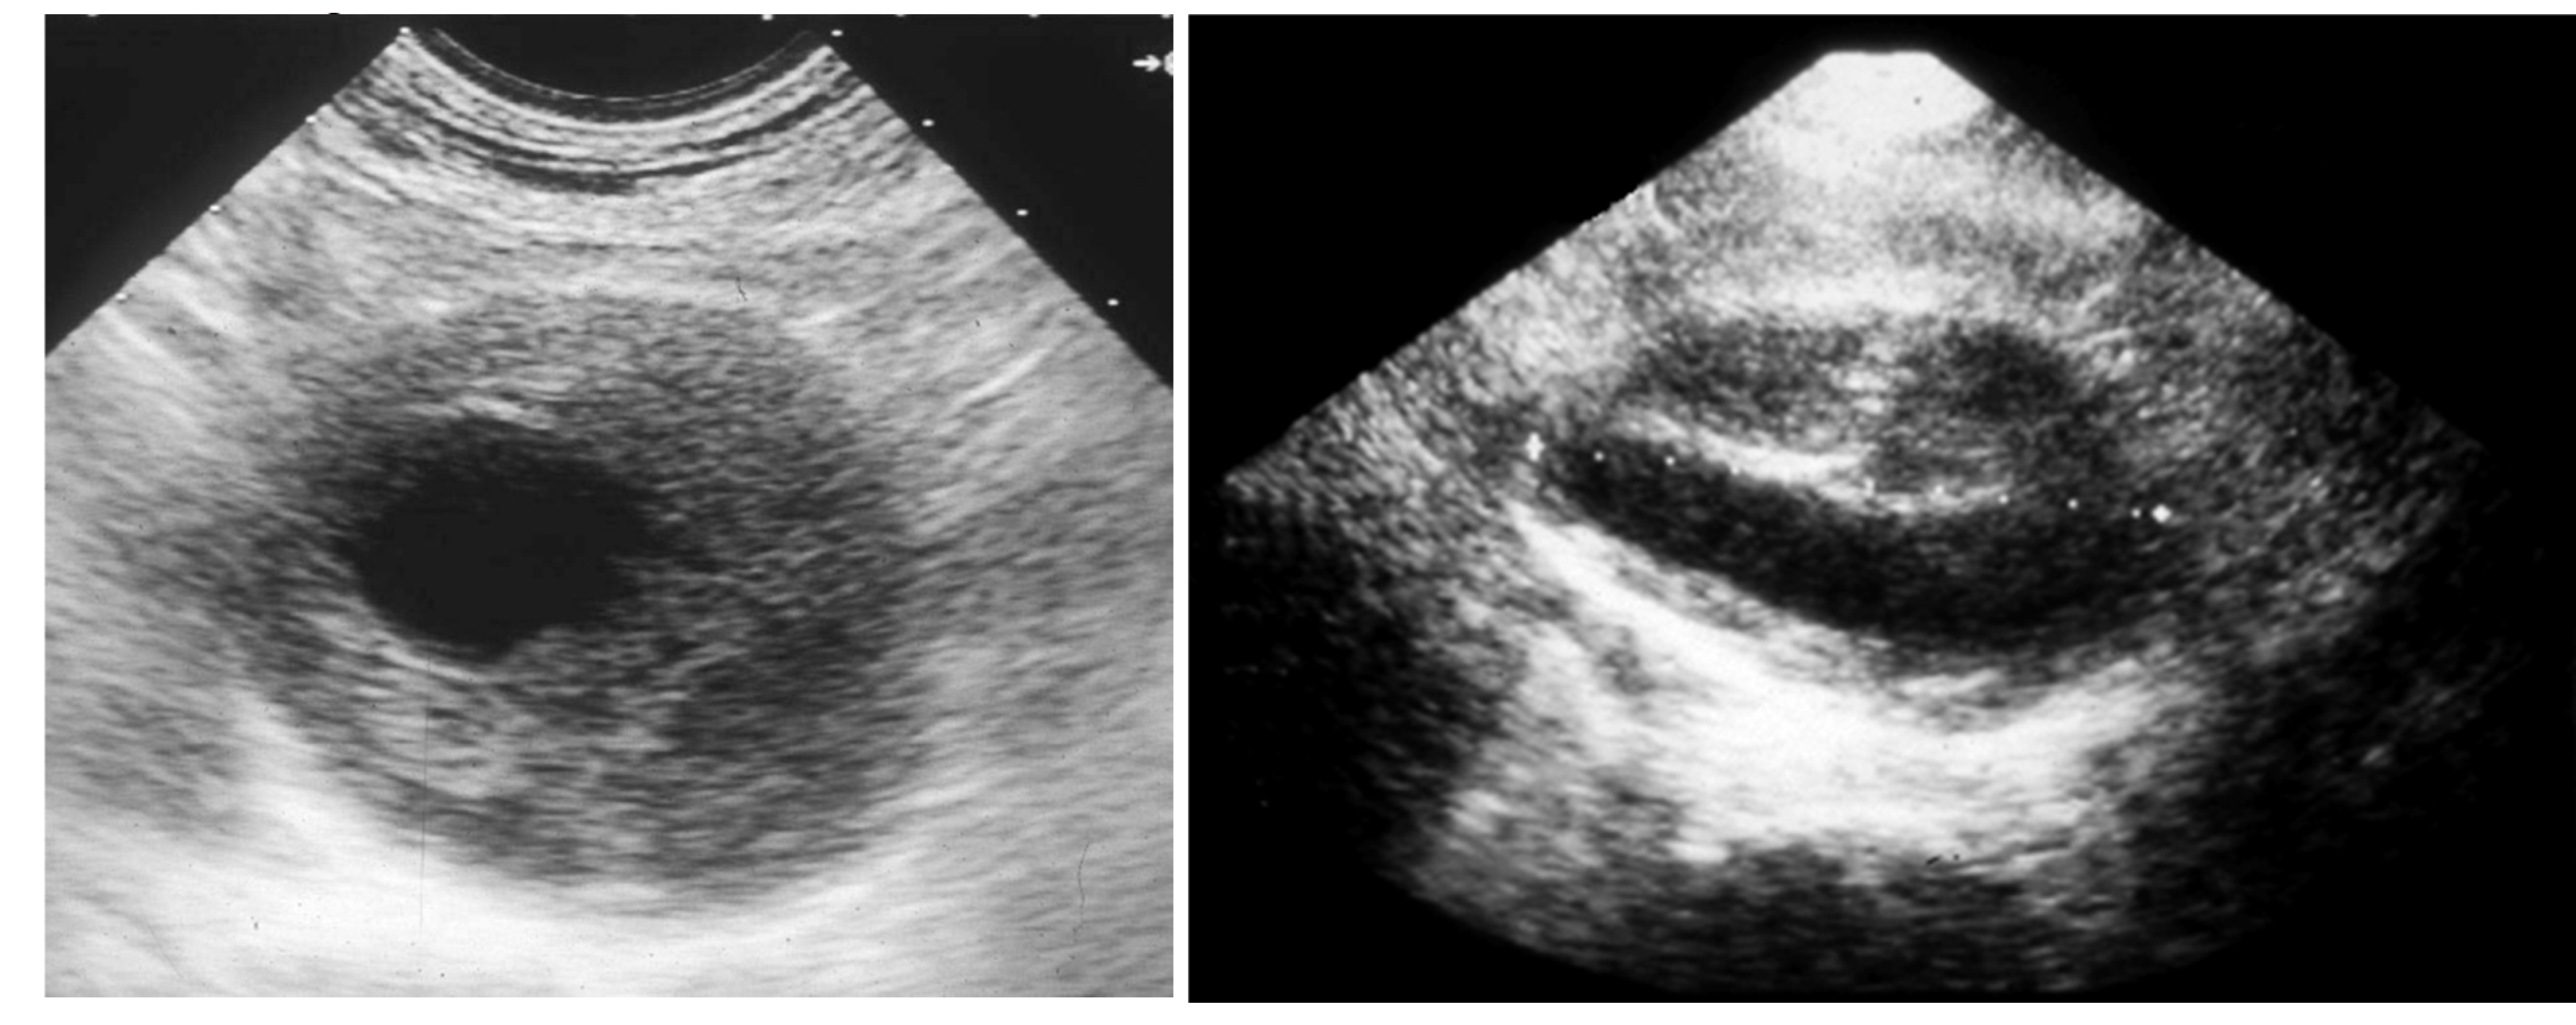

Then, the eventual clinical suspect of an AAA needs to be confirmed by a first-level investigation, such as a duplex scan, which has a very high specificity (almost 100%) and sensitivity (95%) to detect an AAA (Figure 3) [4].

Figure 3. Duplex scan of the abdominal aorta can easily confirm the clinical suspect of abdominal aortic aneurysm. Short axis (left) and long axis (right) view.